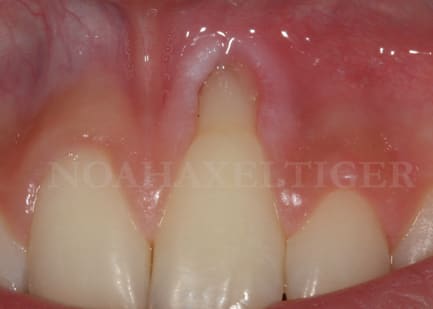

noahaxeltiger-olivier

13/02/2009 à 20h30

lors de la cicatrisation on remarque une amélioration gingivale au niveau de 32 et 42 mais malheureusement une récession persistante au niveau de 31 et surtout 41.

Lors de l'analyse des différents facteurs de cicatrisation, je note alors que 31 et surtout 41 sont mobiles grade 1 !!

Du coup, controle occlusal, contention et opération numero 2 (date de la semaine dernière) :